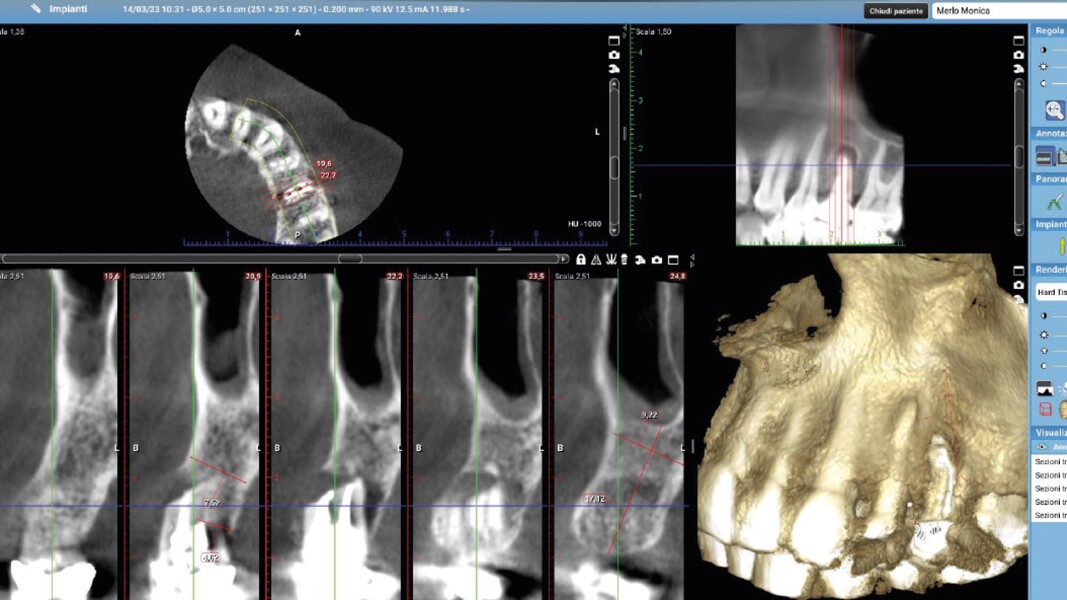

Una paziente di 50 anni presentava un premolare superiore non recuperabile. Dopo CBCT preoperatoria (T0) (Fig. 1), si è proceduto all’estrazione atraumatica e alla gestione dell’alveolo mediante posizionamento vestibolare di una membrana corticale eterologa (Lamina fine 0,7 mm, 35 × 15 mm, OsteoBiol) e riempimento con spugne di collagene (Figg. 2, 3). Sono stati applicati punti di sutura in nylon non riassorbibile 4/0. Dopo sei mesi di guarigione, una nuova CBCT (T1) ha consentito la valutazione della qualità ossea. Per la fase implantare è stato eseguito un lembo secondo la tecnica del roll flap, con preservazione delle papille interdentali e aumento del tessuto cheratinizzato (Fig. 4). È stato inserito un impianto JD Evolution Plus (4,3 × 11,5 mm) ottenendo un’eccellente stabilità primaria. Durante la chirurgia è stato prelevato un campione osseo per analisi istologica (Fig. 5).  Il lembo è stato suturato con nylon 4/0 intorno all’abutment di guarigione. Dopo due mesi, la paziente è stata riabilitata con una corona monolitica in zirconia realizzata da impronta digitale intraorale (Fig. 6).

Il protocollo chirurgico ha seguito i principi della tecnica LAR, prevedendo una gestione stratificata dei materiali rigenerativi al fine di ottenere stabilità volumetrica e controllo biologico del sito post-estrattivo. La membrana ossea eterologa ha fornito un supporto rigido e stabile per la rigenerazione ossea e il mantenimento dei contorni alveolari. Le spugne di collagene sono state scelte per la loro biocompatibilità e capacità di favorire emostasi e rigenerazione tissutale. Le misurazioni dello spessore osseo sono state effettuate su CBCT a T0 e T1 in tre punti:

1. porzione coronale;

2. terzo medio;

3. terzo apicale.

L’analisi CBCT ha evidenziato un mantenimento del volume osseo con valori comparabili tra T0 e T1.

• T0: larghezza 9,22 mm, altezza 17,12 mm;

• T1: larghezza 9,46 mm, altezza 17,02 mm.